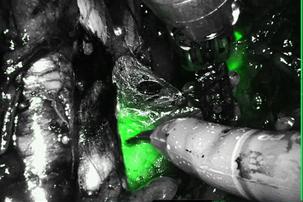

Herbert F Gretz MD performs Robotic Surgery in White Plains. Da Vinci robotic surgery procedures and hysterectomy for benign and cancer conditions. ​